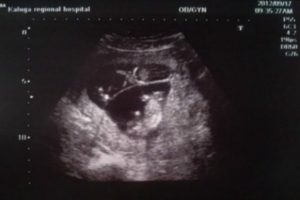

УЗИ не показывает двойню на ранних сроках: один малыш прячется за другим или у женщины будут близнецы, во втором случае оплодотворенная яйцеклетка разделится позже. Если сонолог на УЗИ сразу не увидел двойню, это не говорит о допущенной ошибке.

Количество плодов определяется на первом ультразвуковом скрининге в 12-13 недель. Врач определяет: число плацент, наличие или отсутствие специальной перегородки, сердцебиение плодов. Двойня на УЗИ по фото выглядит как 2 эмбриона с обособленным или совместным амниотическим мешком.

Разнояйцевая двойня на УЗИ

Первые симптомы беременности женщина ощущает уже после задержки. Беременная интересуется расположением будущего ребенка в матке. Разглядеть двойную беременность можно с 8 недели.

Если в матке одновременно прикрепилось несколько оплодотворенных яйцеклеток или развивается однояйцевая двойня, ультразвуковая диагностика зафиксирует несколько сердцебиений.

Однояйцевая двойня на УЗИ

Для достоверности определения ультразвуковое обследование повторяют на сроке 12 недель. Иногда второй эмбрион умирает из-за поглощения одного плода другим, инфекции и так далее.

Ультразвук фиксирует количество эмбрионов в конце первого месяца беременности. 5 неделя — время прикрепления эмбриона к стенке матки. Раннее УЗИ проводится с целью определения типа беременности: маточная или внематочная.

Заключение ультразвукового исследования о количестве развивающихся в утробе плодов устанавливается при выявлении числа плацент, околоплодных пузырей, частоты тонов сердцебиения. Сонолог исследует размер каждого эмбриона.